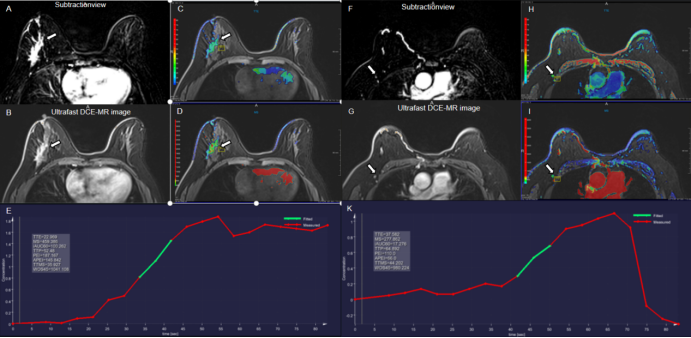

Figure 2. A 36-year-old woman with invasive ductal carcinoma in the left breast with left axillary lymph node metastasis. The irregular heterogeneous enhancing mass and lymph node metastasis in the left breast is shown in the (A, F) early phase MR subtraction images, (B, G) ultrafast DCE images, (C, H) time to enhancement (TTE) maps (C, 17.62s; H, 14.44s), (D, I) maximum slope (MS) maps (D, 6.7%/s; I, 12.9%/s), and (E, K) represent the early time-intensity curves of breast tumor and lymph node, respectively.